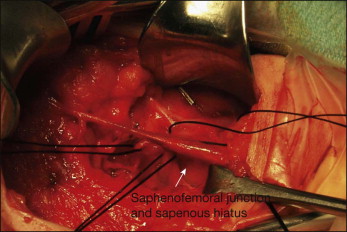

Subarachnoid block (spinal) or general anesthesia is used when classic stripping operations are performed. In the majority of patients, the GSV may be removed using two small incisions. One incision in the groin crease just medial to the femoral pulse usually allows easy exposure of the proximal GSV and saphenofemoral junction ( Fig. 10.9 ). The incision should be large enough to provide adequate exposure to allow a complete and safe procedure, particularly in obese patients, but is usually 3 cm or less in length. The incision should not be made inferior to the groin crease since an inappropriately inferior incision would make control of branches other than the GSV more difficult.

It is appropriate to obtain control of the GSV near the saphenofemoral junction, but to not ligate the vein at this point for reasons that will become apparent later. First, the operator may attempt to identify all other branches, most often including the anterolateral saphenous, external pudendal, superficial epigastric, and circumflex iliac branches ( Fig. 10.10 ). Each of these latter branches is then divided and attempts made to ligate each of their primary branches as well to reduce the risk of persistent or recurrent communication between the deep and superficial venous systems in the groin. The posteromedial aspect of the common femoral vein is inspected, with frequent attendant identification and ligation of a small (2–4 mm) branch in this area that might contribute to recurrences. At the completion of this portion of the operation, the axial GSV is the only remaining unligated branch at the saphenofemoral junction.